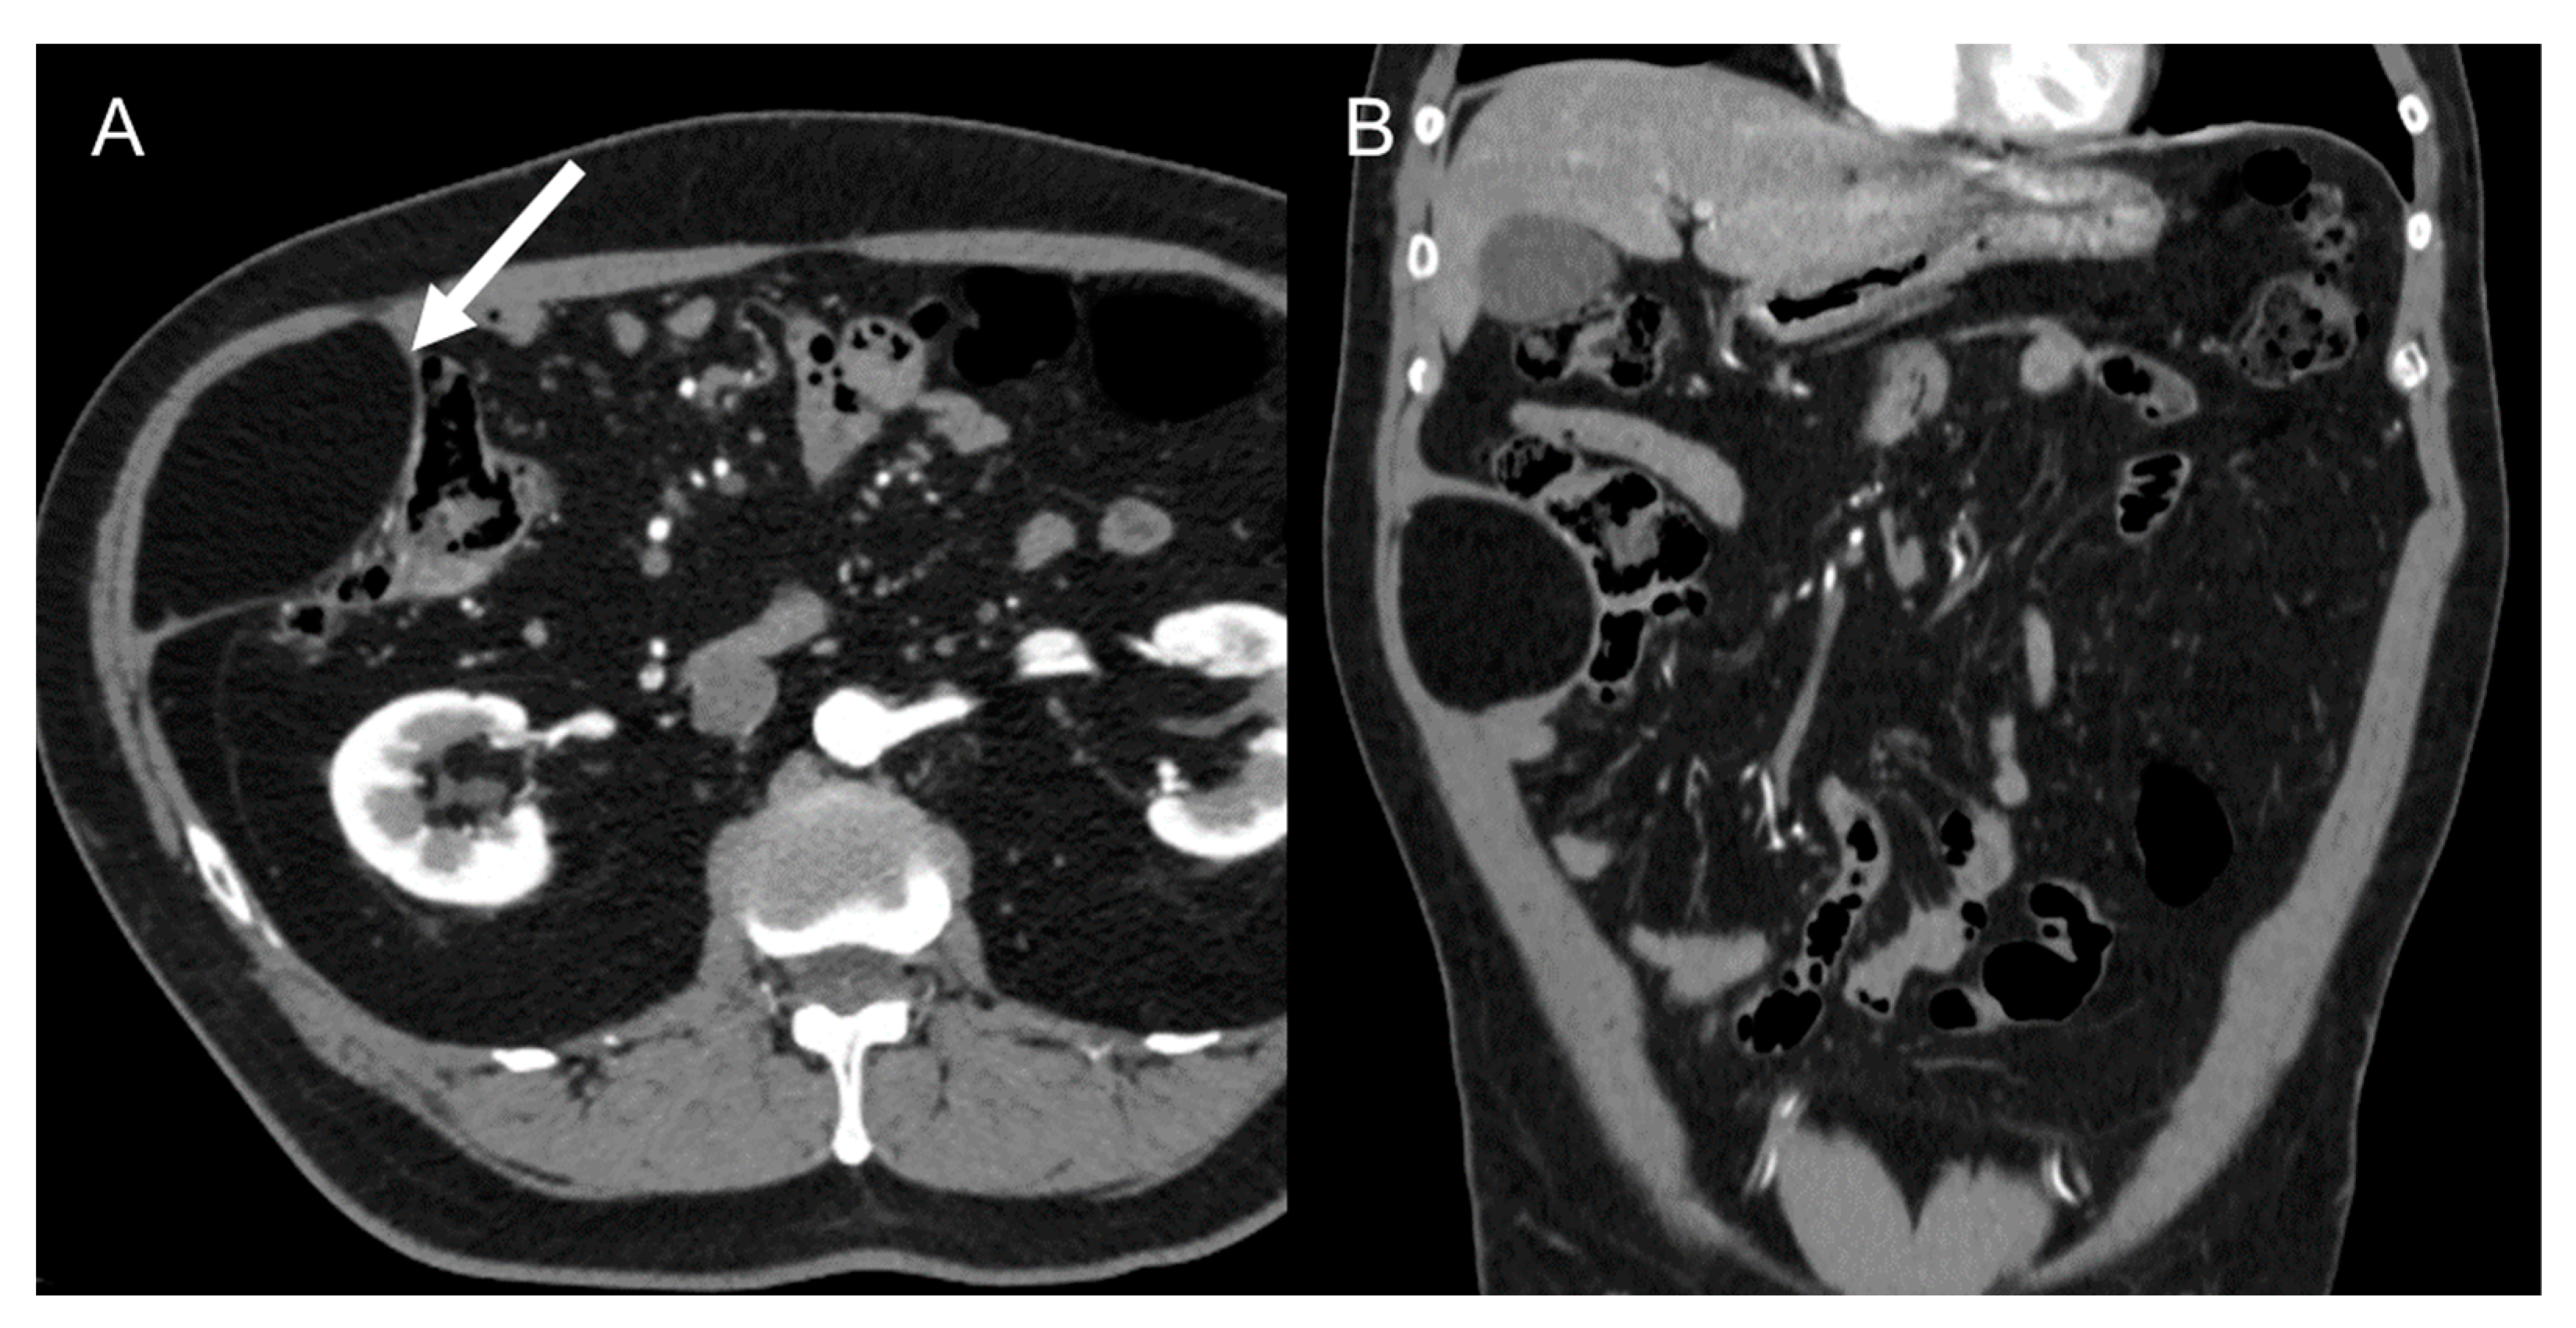

LMS is a smooth muscle tumor [38], more common than LPS in younger age groups [6]. Its most frequent location is the retroperitoneum, near the inferior vena cava [43]. LMS are heterogeneous masses (Figure 4), with irregular peripheral enhancement and enhancing solid portions, mixed with cystic, hemorrhagic, or necrotic areas. LMS show marked T2 hypointensity on MRI and are similar in attenuation to uterine myometrial smooth muscle on CT [39]. Fatty components and calcifications are usually absent [34,38]. The evidence of a large, heterogeneously enhancing, necrotic retroperitoneal mass contiguous with a vessel, with extra- and intraluminal involvement, is highly suggestive of LMS [12,37,43]. It could stem from the inferior vena cava, extending into the intrahepatic portal veins or superior mesenteric vein, or even from small vessels such as renal or gonadic veins. Differentiation from extrinsic compression can be challenging [12,40].

Figure 4.

Retroperitoneal leiomyosarcoma in a 63-year-old woman. Axial (A) and coronal (B) CT images on venous phase show a 10.2 cm heterogeneous mass with central area of low attenuation consistent with necrosis (arrow).